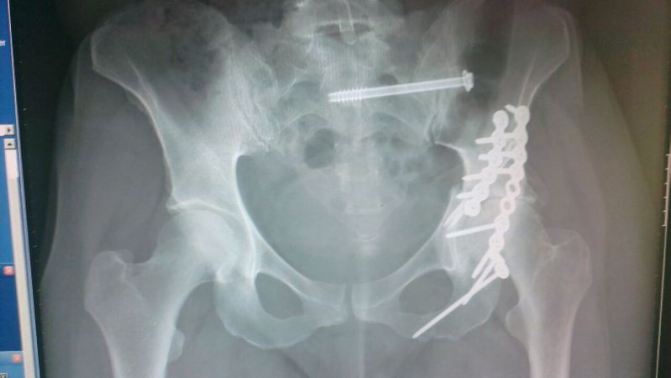

I was bed-bound and on traction for a time after a serious RTA in 2012. Then after major surgery to put me back together, the real hard work started. The physio became my new best friend and my new worst nightmare in equal measure as I had to learn to just put one foot in front of the other.

I can honestly say I would not be doing half the activities I am now if it wasn’t for our fantastic NHS. In the first instance the critical care teams – consultants, nurses, my top trauma surgeon and finally and just as important the Physiotherapists in hospital and ongoing over the years.